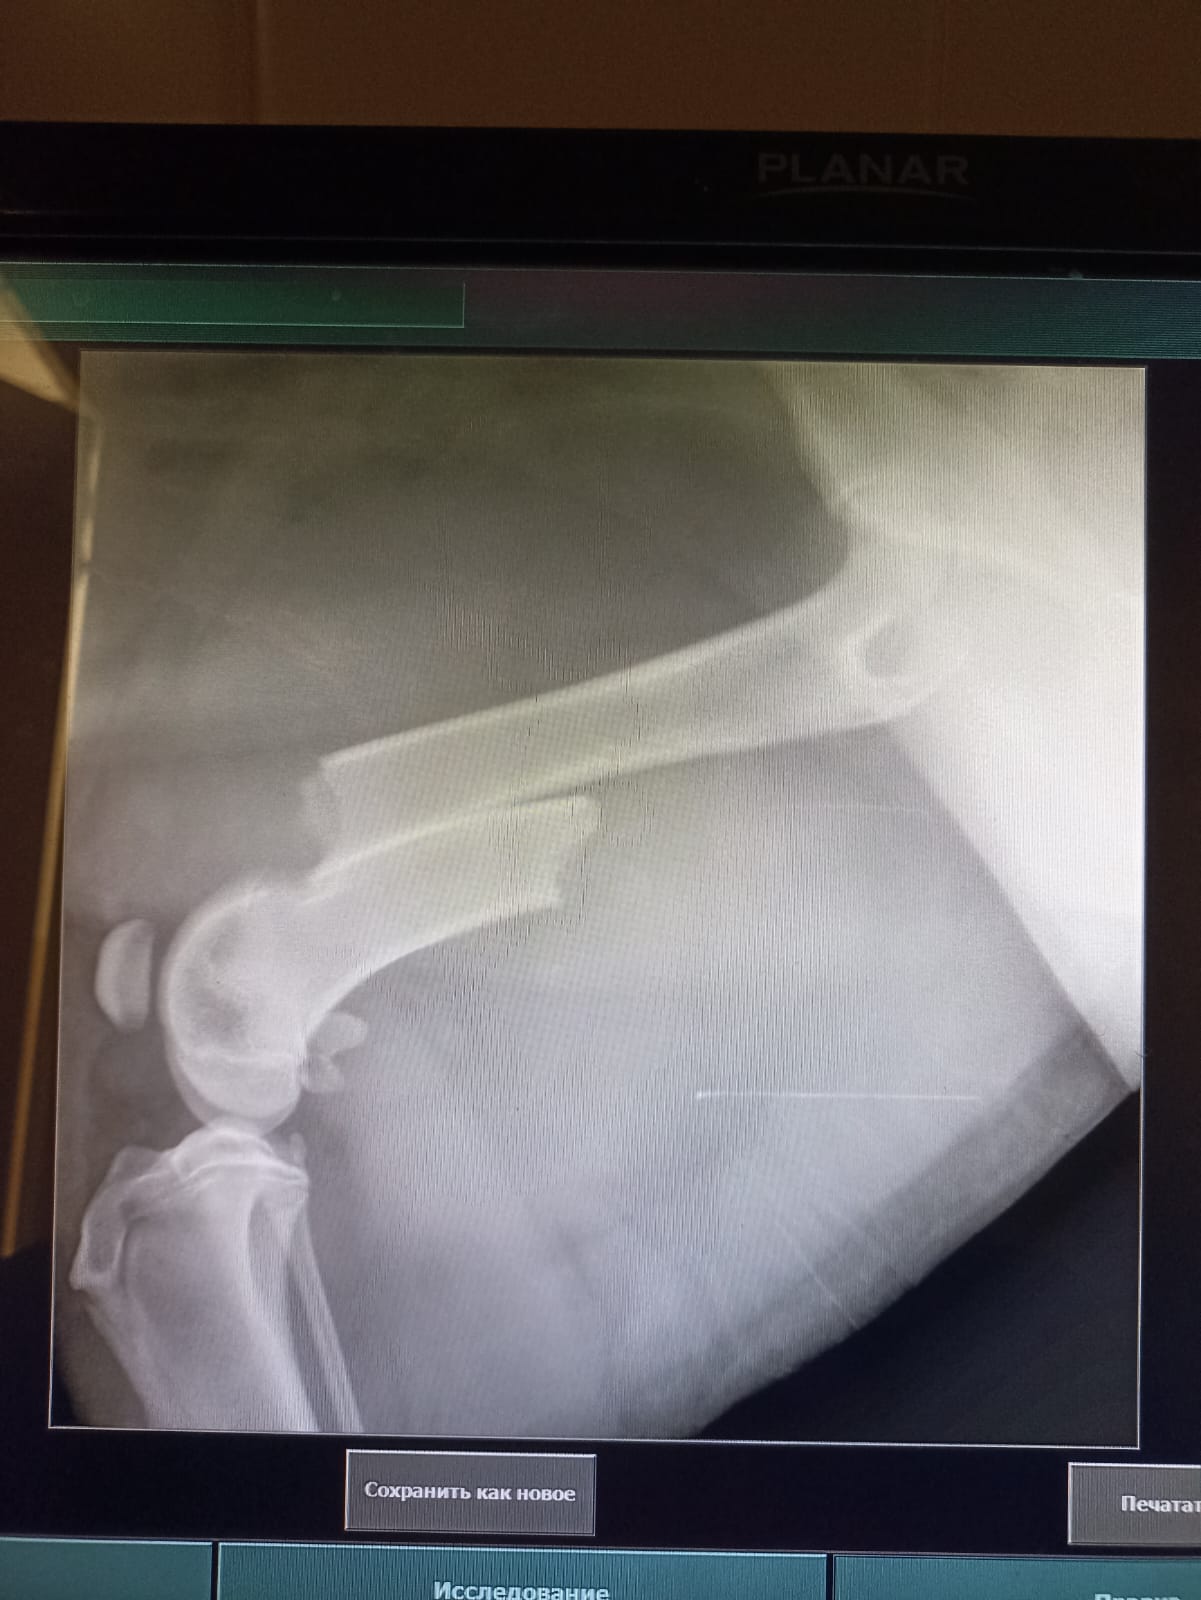

Волонтёр привела молодую суку ризена со сломанной лапой в клинику к Насте pani Stasi. Вроде перелом не сильно свежий.

Ногу будет хирург смотреть и может в ближайшее время прооперируют.

Собаке 8 месяцев, хозяйка попала в реанимацию.

Её забрала заводчица. И что-то там у них случилось, то ли лошадь понесла, то ли что, в общем, собака перепрыгивала через телегу и сломала лапу. У заводчицы тоже ключица сломана, может ещё что-то.

Ветеринар позвонила знакомому волонтёру, говорит, чего усыплять, я её соберу, рентген только надо.

Операцию сделали, собрали лапу на две пластины. Выписка попозже будет.

Да, задняя правая сломана.